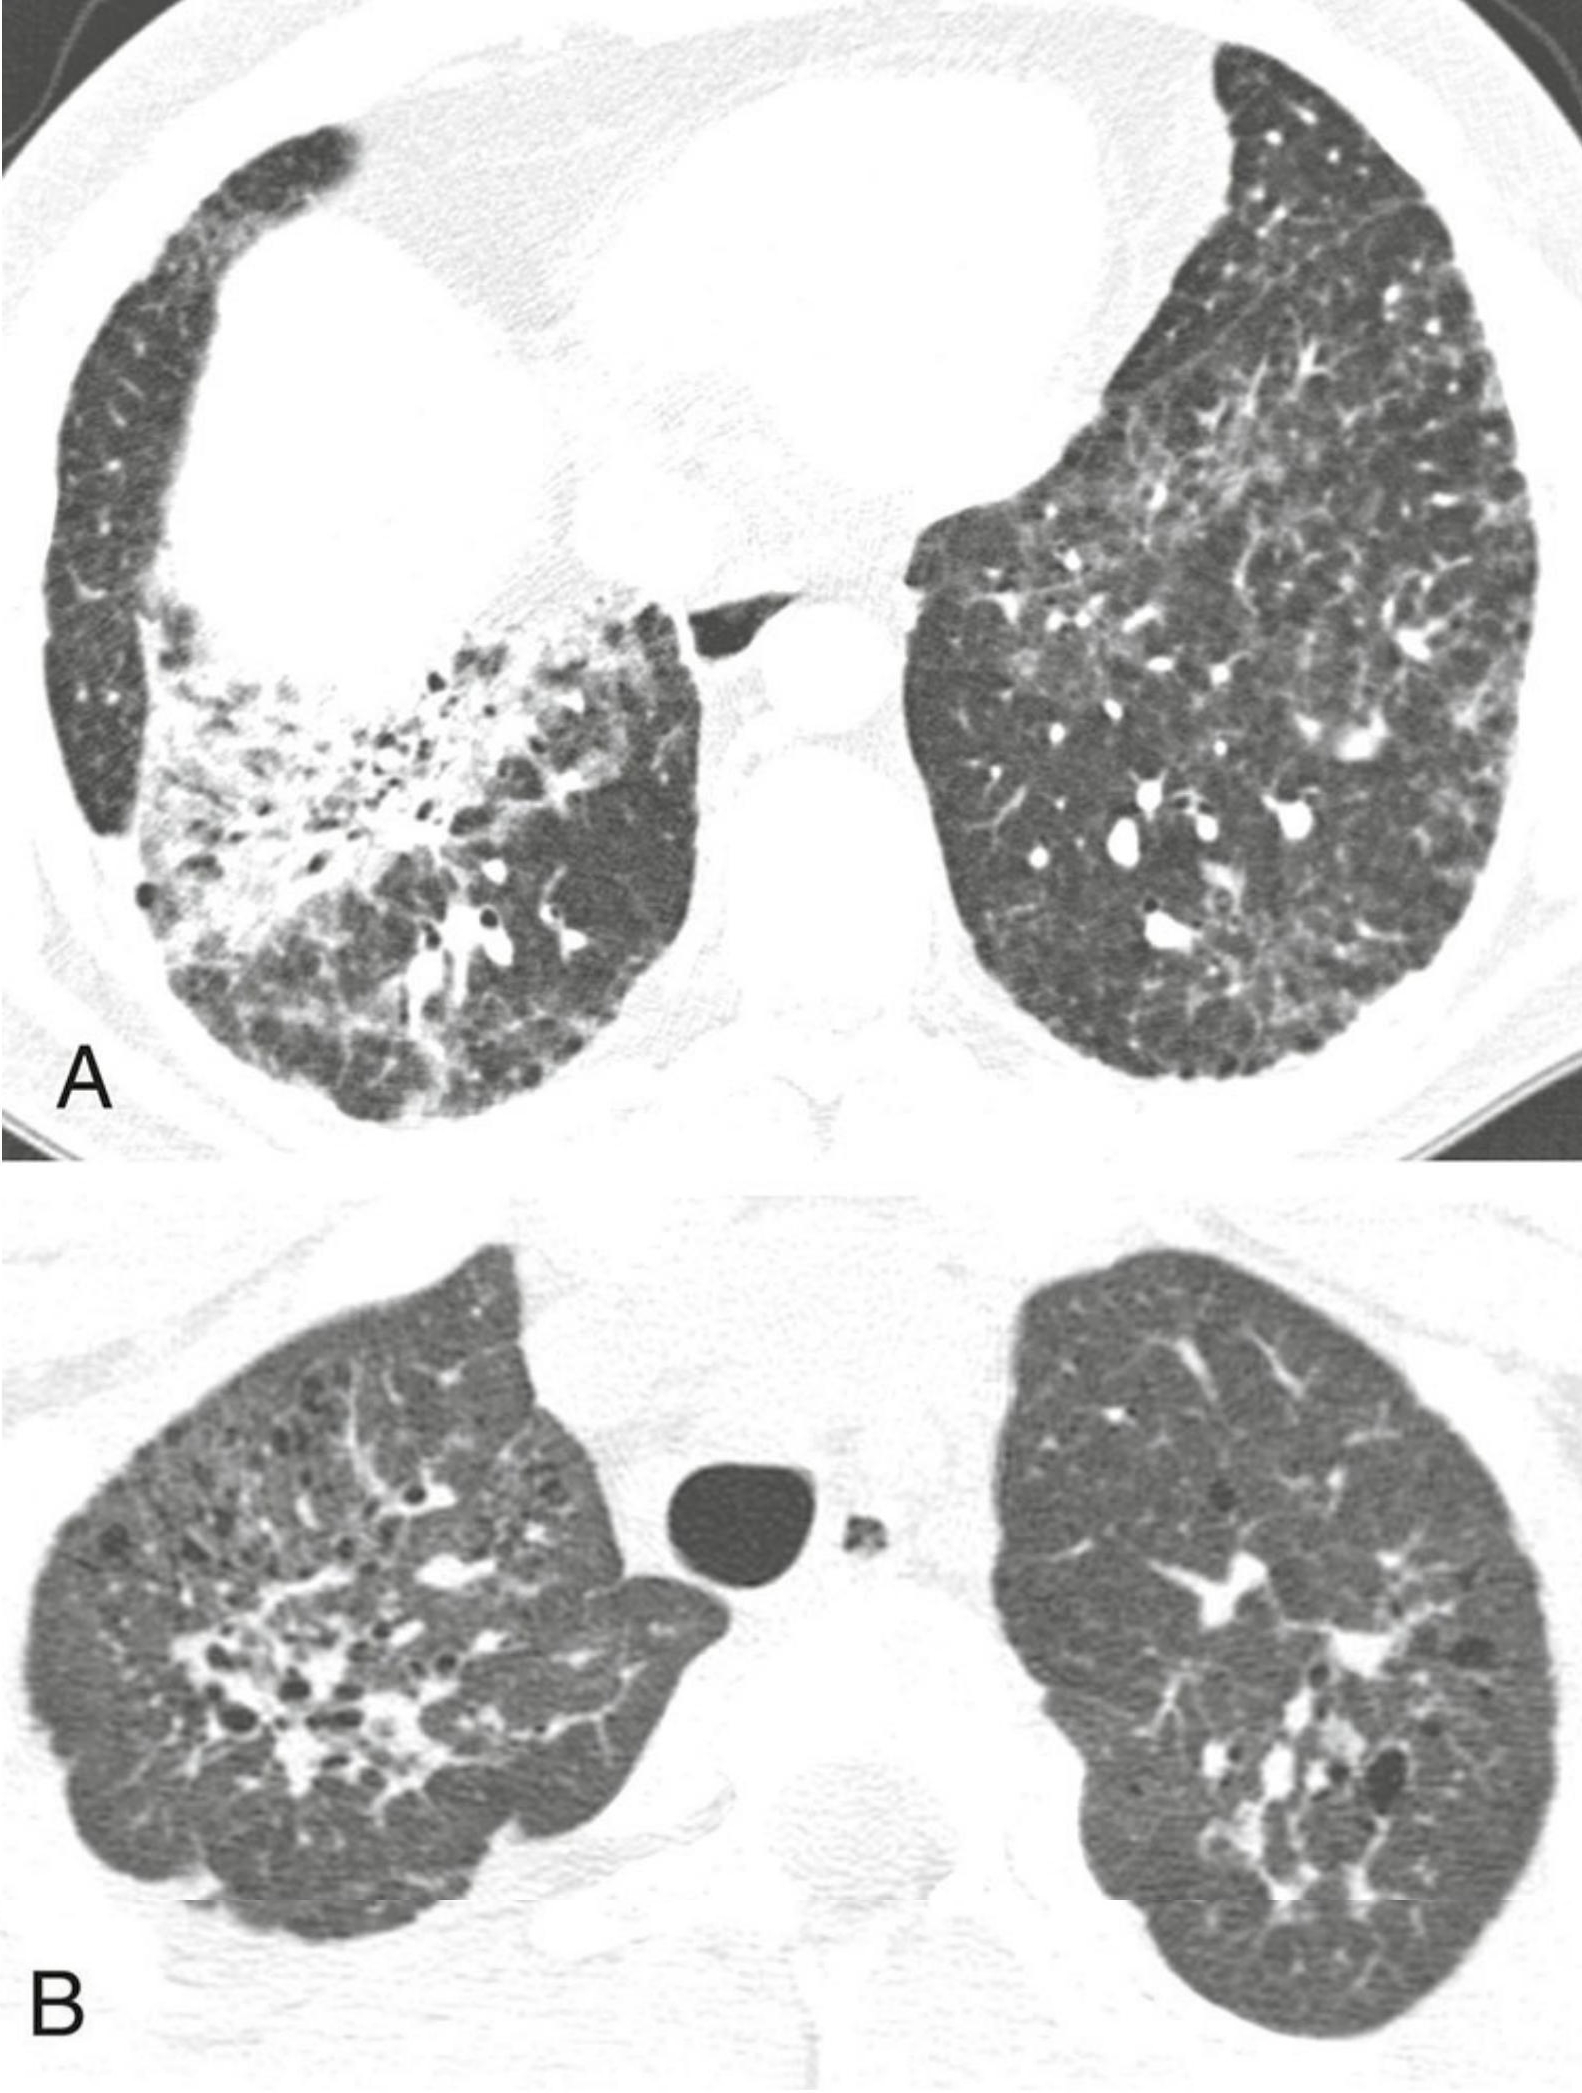

27548bcf9c93bc25a1cd816613e8485a.png

纤维化型非特异性间质性肺炎(NSIP)的典型表现。

4例纤维化型NSIP,每例均显示不规则网状影(蓝箭)和牵拉性支气管扩张(红箭)为主要异常。紧邻胸膜下肺区不受累(A至C)高度提示本病,但有时无此征象(D)。蜂窝征缺如或不明显。

NSIP的分布与UIP相似,以胸膜下和肺基底分布为主。但是,若病变呈肺外周、向心性分布而紧邻胸膜下肺区相对不受累,则高度提示NSIP,该表现见于20%~50%的病例。NSIP也可表现为支气管血管周围分布为主。